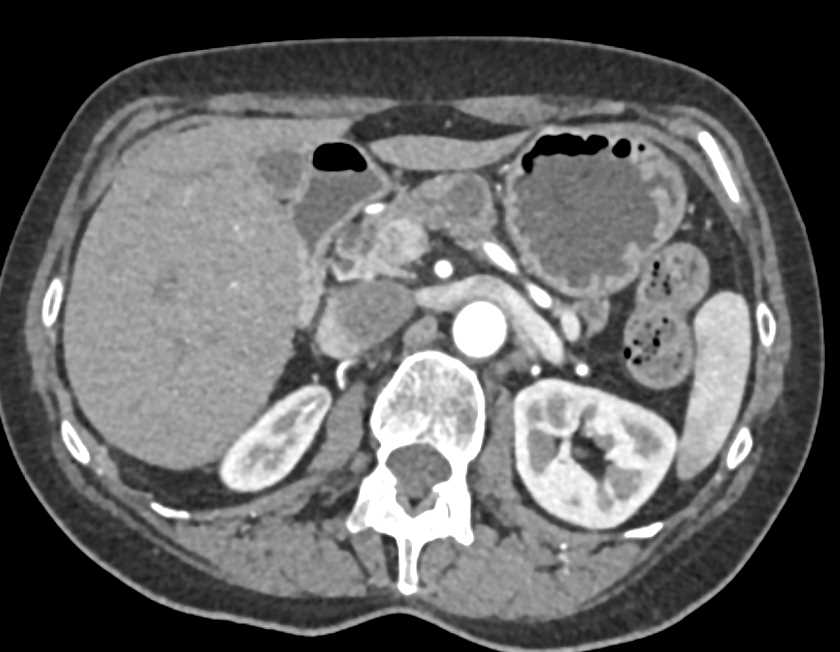

Necrotizing Pancreatitis with Extensive Air in Pancreatic Gland